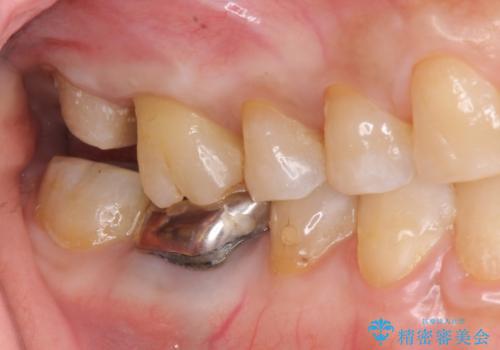

歯髄方向 歯肉方向へと深い 2種類の大きな虫歯

#17は失活歯で歯肉方向への縁下カリエス、#16は生活歯であるものの歯髄ギリギリの処置となるであろうとが予想される治療です。